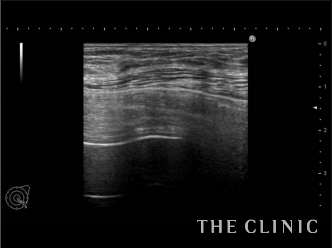

エコー画像でもしこりがきれいになくなったことが確認できます。